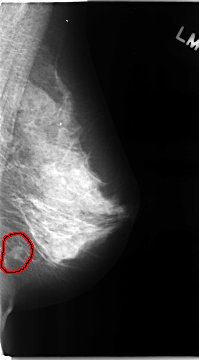

C_0104_1.RIGHT_MLO

RIGHT_MLO LINES 4672 PIXELS_PER_LINE 2632 BITS_PER_PIXEL 12 RESOLUTION 50 OVERLAY

FILE: C_0104_1.RIGHT_MLO.OVERLAY

TOTAL_ABNORMALITIES 1

ABNORMALITY 1

LESION_TYPE MASS SHAPE OVAL MARGINS CIRCUMSCRIBED

ASSESSMENT 3

SUBTLETY 5

PATHOLOGY BENIGN

TOTAL_OUTLINES 1

BOUNDARY